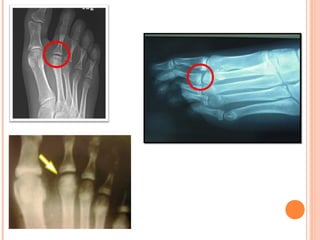

Enfermedad de Freiberg o Kohler II

 Destrucción   de   cabeza   de   2do

Cuadro Radiológico

   Rx sucesivas = destrucción gradual de la epífisis

metatarsal.

   Carilla   articular    deformada,     irregular,

ensanchada, agrietada y finalmente aplanada.

   Cabeza metatarsiana ensanchada en sentido

transversal y disminuida de altura.

   Espacio articular aparece muy aumentado.